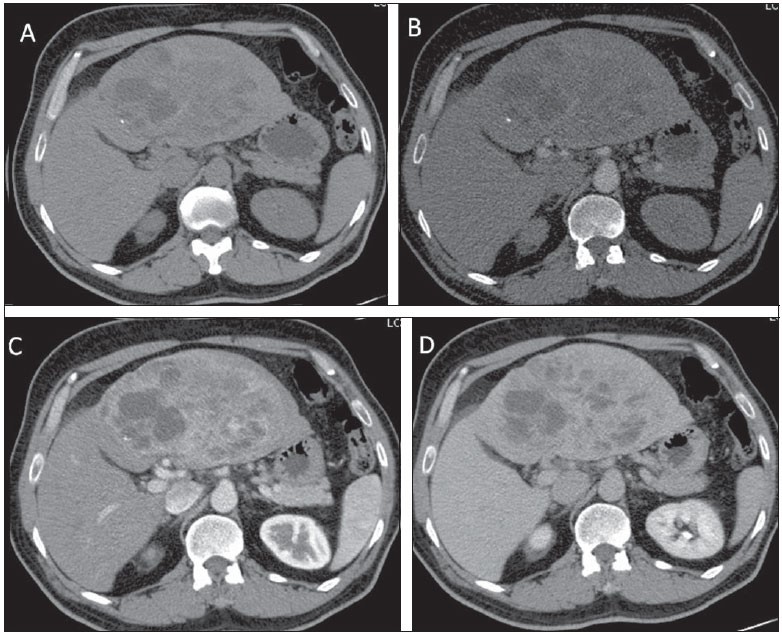

- tomografia com cortes finos para pâncreas com protocolo trifásico observa massa heterogênea, hipocontrastante em relação ao pâncreas ao redor, atrofia da glândula e dilatação do ducto de wirsung e hepatocolédoco. Ela permite estadiamento para avaliar a invasão de vasos importantes como artéria mesentérica, tronco celíaco, veia mesentérica-porta; além de gânglios linfáticos e metástases hepáticas (fígado) ou peritônio;

- tomografia e ressonância. Como os PNETS são altamente vascularizados costumam se apresentar como tumores hipercontrastantes após administração de contraste na fase arterial apresentando coloração mais clara que o pâncreas ao redor tanto na tomografia quanto ressonância. Também pode ser realizados: o Octreoscan (Cintilografia com receptores para Octreotide) e a Cintilografia com Gálio 67;

Metastases são raras e correspondem a 2 % de todos canceres pancreáticos oriundas do câncer colorretal, pulmões, mama e melanoma. A maioria é assintomática e é descoberta por exame de imagem. Em geral, são altamente vascularizados costumam se apresentar como tumores hipercontrastantes após administração de contraste na fase arterial apresentando coloração mais clara que o pâncreas ao redor tanto na tomografia quanto ressonância. A biopsia por eco-endoscopia com punção pode dar diagnóstico, mas não é necessária na lesão isolada.